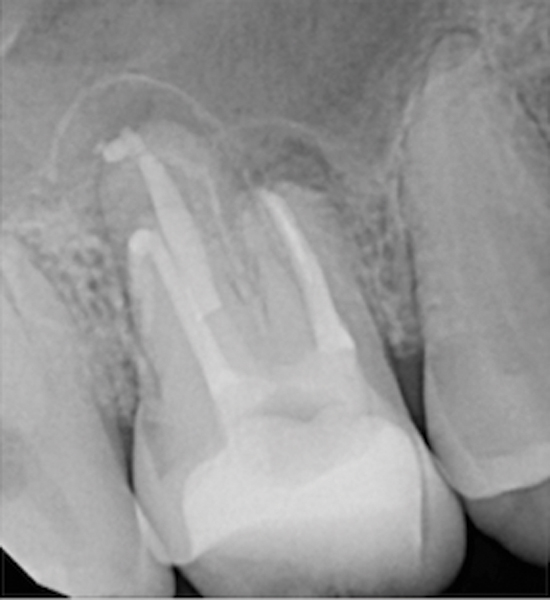

Fig 15. Preoperative radiograph. Courtesy of Dr. Sam Kratchman.

Fig 16. Post apicoectomy. Courtesy of Dr. Sam Kratchman.

Fig 17. Retropreps and isthus filled. Courtesy of Dr. Sam Kratchman.

Fig 18. 20-month follow-up with BC putty shows complete healing. Courtesy of Dr. Sam Kratchman.

Case 3: Apicoectomy and Retrofill